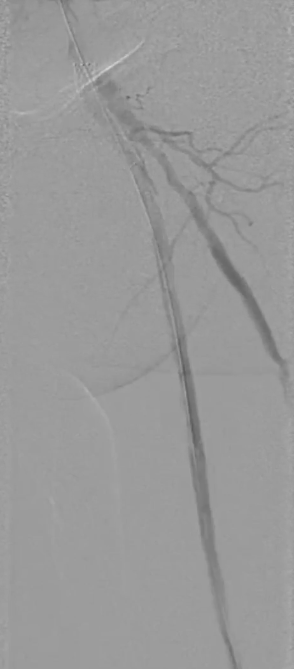

栓塞处理:造影发现管腔获得尚可,但是流速明显较慢,考虑保护伞上方管腔闭塞(考虑斑块/血栓脱落),用6F导管反复抽吸后收回保护伞。

夹层发现及处理:

更换V18导丝后造影显示,胫后动脉血流通畅,胫前动脉疑似仍有小的血栓脱落,导致栓塞。

股浅动脉全程管腔获得尚可,但中段有明显的夹层形成,

先用5mm长球囊充分预扩张;再次造影显示,股浅动脉近中段管腔获得良好,中远段仍有大量的夹层

采用药物涂层球囊(DCB)对股浅动脉病变段全程覆盖:近端用5-250新型药涂球囊,远端用5-150 impact 药涂球囊;

造影显示中段仍有局限性夹层,为保证远期通畅率,植入补救性支架并以5mm球囊后扩张